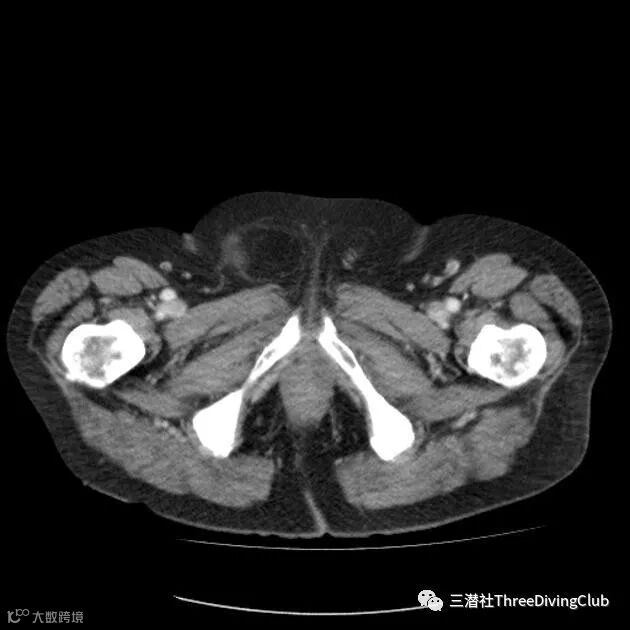

膀胱挤压

水的挤压是一方面,另一方面来自紧身的湿衣,膀胱受到间接压力后会刺激括约肌,产生尿意